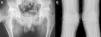

Reporte de casoPaciente varón de 17 años de edad; a los 13 años presentó dolor de cadera derecha y de rodilla izquierda. Cinco meses más tarde presentó inflamación de ambas rodillas y de interfalángicas de la mano derecha. El paciente refirió historia de dificultad al caminar desde los 3 años de edad. El examen físico mostró un adolescente con marcha anormal, escoliosis espinal y cifosis de la columna torácica. La movilidad de la columna lumbar, coxofemorales, rodillas, tobillos e interfalángicas de la mano derecha estaba severamente limitada. Las radiografías de manos y pies (fig. 1a y b), caderas y rodillas (fig. 2a y b) revelaron osteopenia difusa, ensanchamiento tubular de las epífisis y pérdida del espacio articular, sin lesiones erosivas; las radiografías de cadera y rodillas mostraron además cambios degenerativos, con cabezas femorales ensanchadas. Las vértebras torácicas y lumbares, con vértebras aplanadas e irregularidades en las mesetas vertebrales (fig. 3a y b). La proteína C reactiva y la velocidad de sedimentación globular eran normales.

La DPSR simula clínicamente una artritis idiopática juvenil en etapas tempranas1,2; sin embargo, las evidencias que establecen el diagnóstico de esta displasia ósea son la afectación articular no inflamatoria y los hallazgos radiológicos característicos, como la presencia de epífisis ensanchadas, osteoporosis generalizada y platispondilia3.